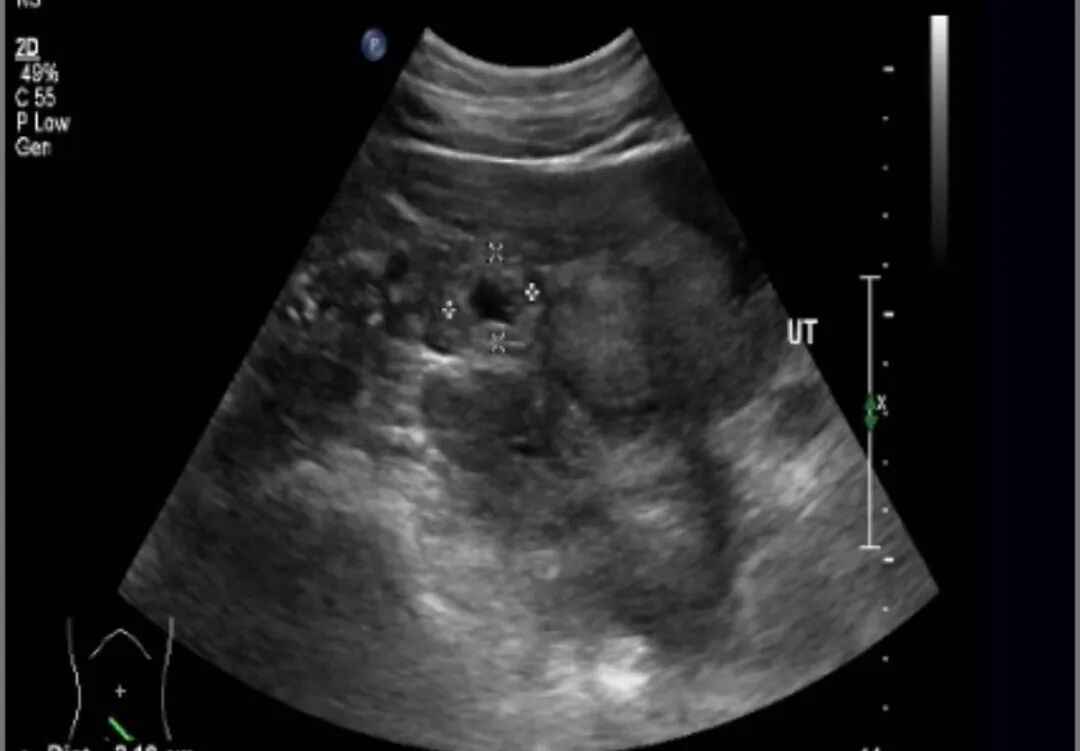

患者因突发剧烈腹痛急诊入院,入院时已面色苍白、头部下垂、生命体征濒临崩溃。夜班主治医师朱俊晓凭借丰富的临床经验,结合急诊超声检查,迅速确诊为右侧输卵管间质部妊娠破裂——这是宫外孕中最凶险的类型,该部位血运丰富,破裂后出血迅猛,短时间内即可致命。 面对患者年龄、异位妊娠处解剖学结构的特殊性及病情的危急程度,朱俊晓当机立断:“立即启动应急预案!”,妇科、麻醉科与手术室迅速联动,决定采用腹腔镜辅助下右输卵管切除+妊娠物切除。这一决策既确保了病灶的彻底清除,又避免了二次手术风险。 由于患者出血量极大,团队果断启用了自体血回输技术,将术中流失的血液过滤净化后即时回收。手术室内,团队成员各司其职,紧密配合,在腹腔镜进入腹腔的瞬间,大量积血涌出,朱俊晓医生迅速找到破裂部位,精准施术,控制出血点。经过1小时紧张奋战,共回输自体血1159ml,患者血压逐步回升,生命体征趋于平稳。 “这次成功抢救,关键在于快速诊断、及时手术和自体血回输技术的应用。”朱俊晓介绍,在连续6个夜班中,均遇到了宫外孕病例,且全部成功救治。“宫外孕是妇科常见的急腹症之一,而输卵管间质部妊娠就像一颗定时炸弹,随时可能破裂大出血,危及生命。因此,育龄女性出现停经、腹痛、阴道流血等症状时应及时就医。” 诸城市人民医院妇科作为“全国巾帼文明岗”“国家临床重点专科联盟成员单位”“潍坊市临床重点学科”,始终以卓越的救治能力守护生命防线。该科室组建了一支反应迅速、技术过硬的快速响应团队,依托“黄金1小时”抢救机制,实现了从接诊到手术的无缝衔接。 过去一年,该团队累计接诊妇产科门急诊患者超1.2万人次,成功抢救宫外孕大出血、黄体破裂、卵巢肿瘤蒂扭转等危重病例200余例,腹腔镜下广泛性子宫切除及盆腔淋巴结清扫、子宫内膜癌分期手术、IV期子宫内膜异位症病灶切除术、晚期卵巢癌满意的肿瘤细胞减免术、外阴癌根治术、宫腔镜下II型粘膜下肌瘤电切术、重度宫腔粘连分离术、子宫畸形矫正术等复杂手术800余例,多项核心指标位居山东省前列。 从技术创新到服务升级,诸城市人民医院积极构建了从24小时待命的急诊绿色通道到“一患一策”的全链条救治体系。这些创新举措不仅提升了急危重症救治效率,更让患者享受到了个性化医疗服务。未来,医院将继续以重点学科建设为引领,为守护龙城百姓健康保驾护航。